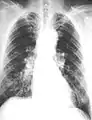

Close-up asbestosis right lower zone ILO 2/2 S/S

The abnormal chest x-ray and its interpretation remain the most important factors in establishing the presence of pulmonary fibrosis.[11] The findings usually appear as small, irregular parenchymal opacities, primarily in the lung bases. Using the ILO Classification system, "s", "t", and/or "u" opacities predominate. CT or high-resolution CT (HRCT) are more sensitive than plain radiography at detecting pulmonary fibrosis (as well as any underlying pleural changes). More than 50% of people affected with asbestosis develop plaques in the parietal pleura, the space between the chest wall and lungs. Once apparent, the radiographic findings in asbestosis may slowly progress or remain static, even in the absence of further asbestos exposure.[25] Rapid progression suggests an alternative diagnosis.